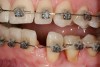

Figure 9: Orthodontic distraction osteogenesis to develop the implant site of tooth No. 23.

Figure 9

This treatment plan was elected with the premise to reevaluate treatment options during orthodontic tooth movement. Soft-tissue augmentation was initiated to correct the mucogingival defect in the area of teeth Nos. 21 and 22. A free gingival graft was performed to achieve an adequate band of attached and keratinized gingiva to resist potential stripping on the root surfaces of teeth Nos. 22 and 21 during orthodontic movement (Figure 8). Orthodontic movement then was initiated to site-develop position No. 23 for an implant (Figure 9 through Figure 11). Orthodontics also was used to idealize the patient’s occlusion and develop canine guidance to minimize occlusal load and maximize the redistribution of forces36-40 for protecting the future implant from deleterious forces. The space was opened around the peg lateral tooth No. 7, and the gingival levels were aligned for maxillary incisors. Bonding was performed to restore the length of teeth Nos. 8 through 10 and to bond the peg lateral to a normal tooth form, which allows the orthodontist to idealize the posterior occlusal scene and maintain canine guidance (Figure 12 through Figure 13).